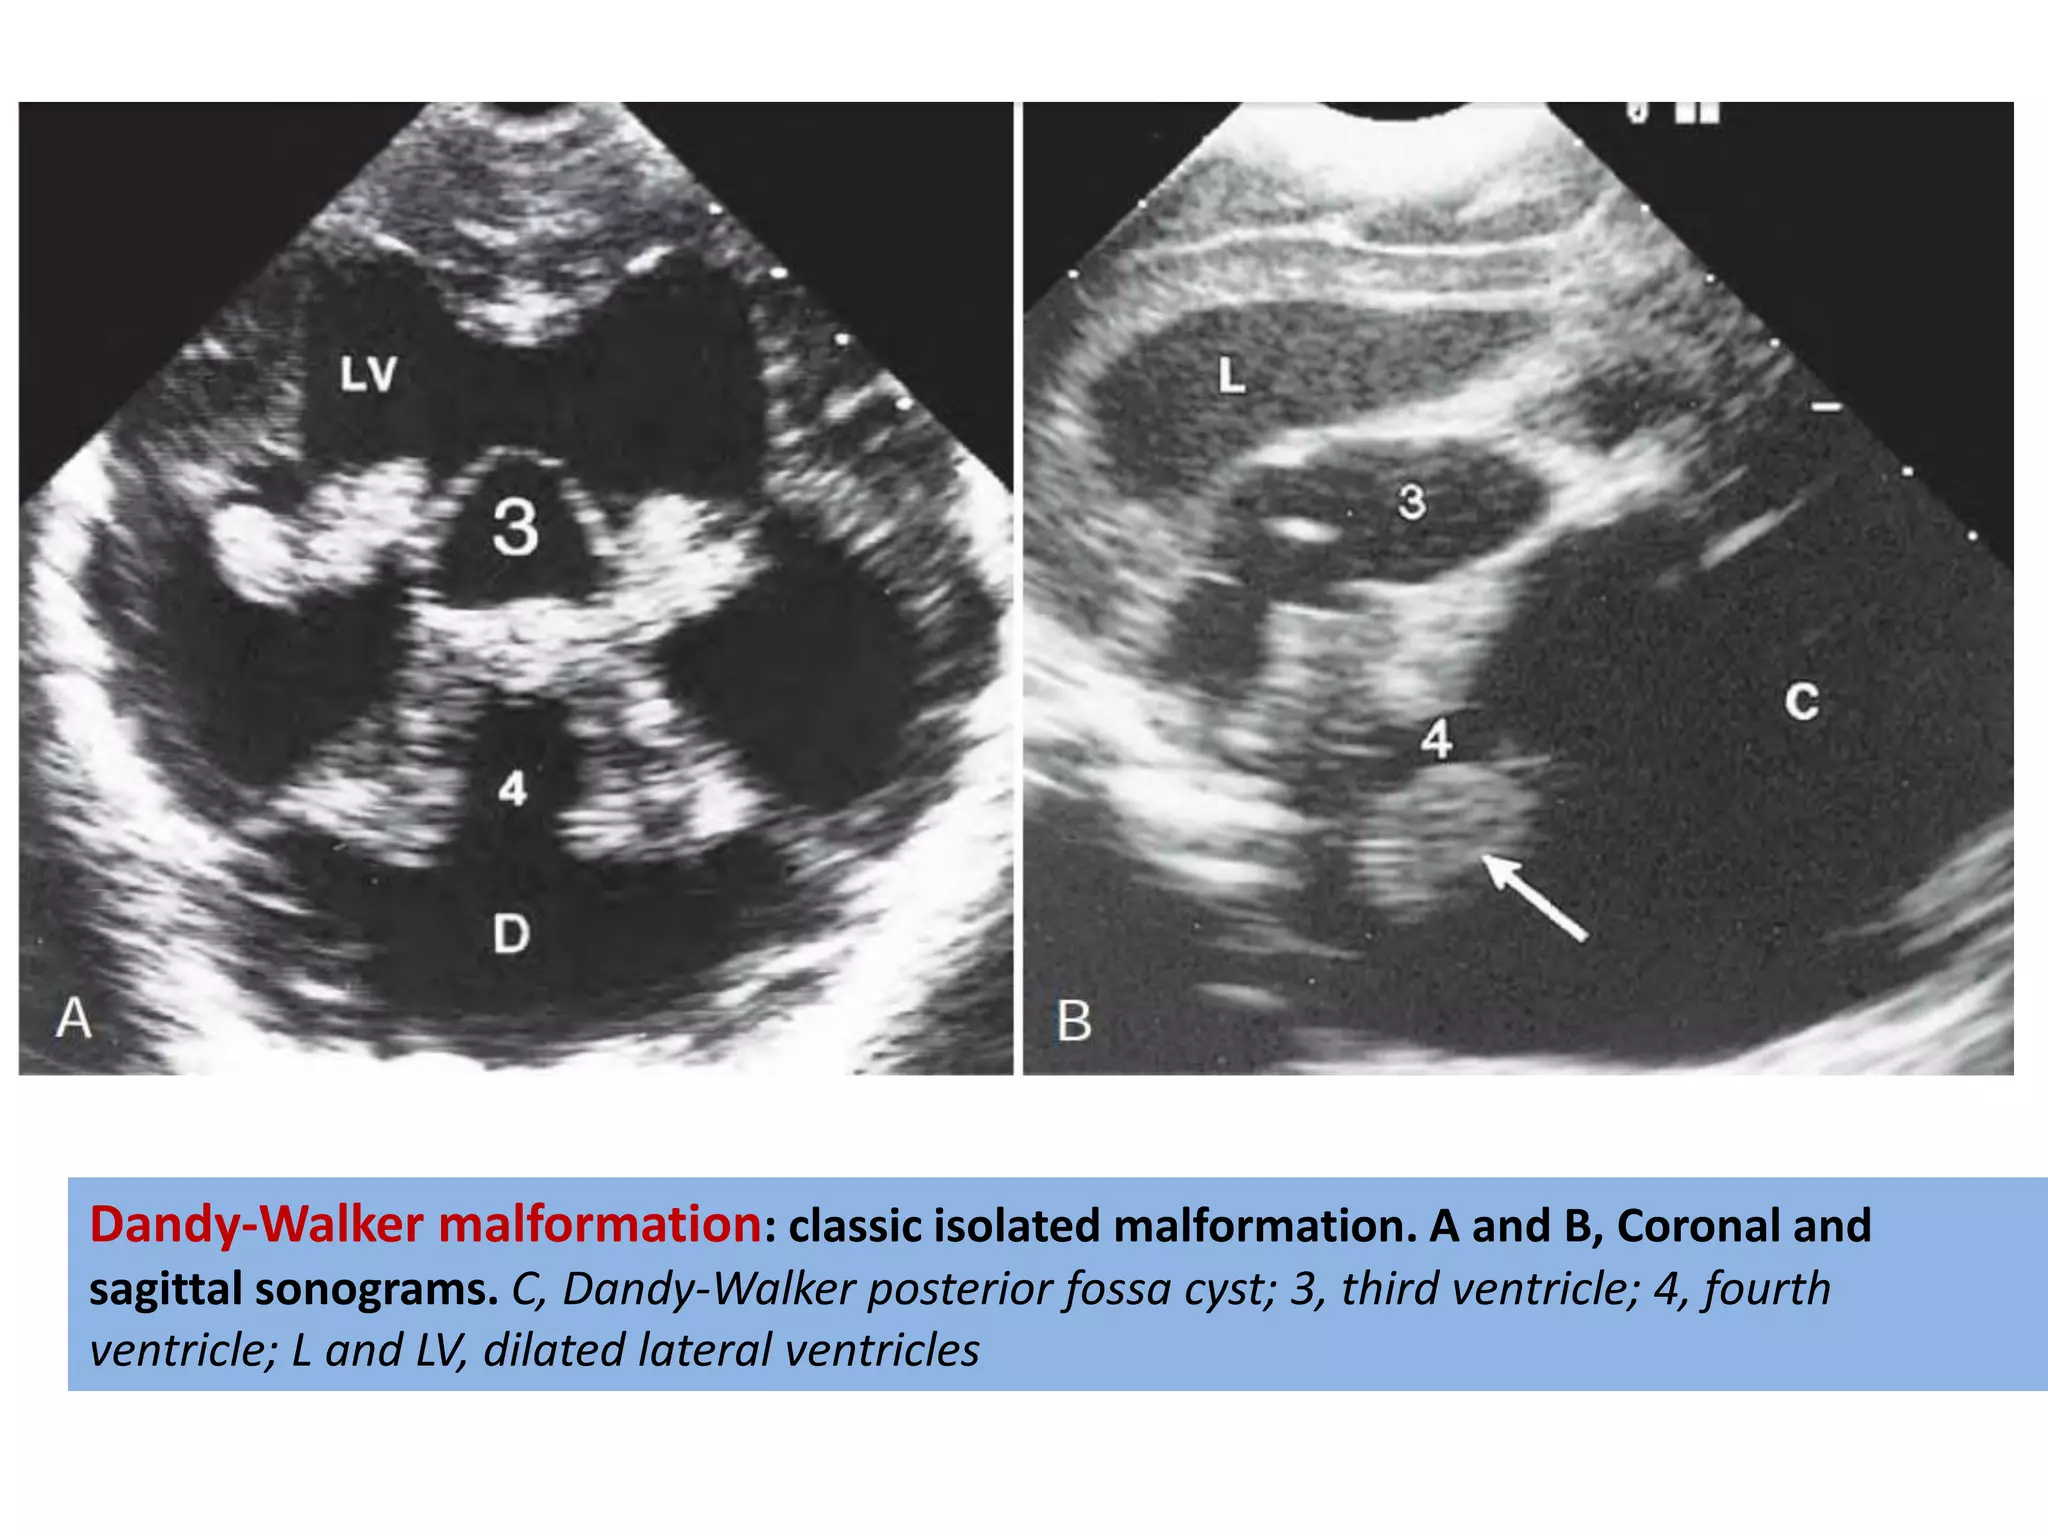

Dandy-Walker Malformation

• Characterised by cystic dilatation of the fourth

ventricle and an enlarged posterior fossa with

upward displacement of lateral sinuses,

tentorium and torcula herophili associated with

varying degree of vermian aplasia or hypoplasia.

• Due to failure of development of anterior

medullary velum( embryonic roof of 4th

ventricular) atresia of fourth ventricular outlet

foramina, and delayed opening of foramen

magendie.

Dandy-Walker malformation: classic isolated malformation. A and B, Coronal and

sagittal sonograms. C, Dandy-Walker posterior fossa cyst; 3, third ventricle; 4, fourth

ventricle; L and LV, dilated lateral ventricles

Dandy-Walker malformation: classicisolated malformation. A and B, Coronal and sagittal sonograms. C, Dandy-Walker posterior fossa cyst; 3, third ventricle; 4, fourth ventricle; L and LV, dilated lateral ventricles